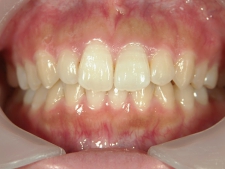

矯正歯科 治療後

矯正歯科 治療後 正面